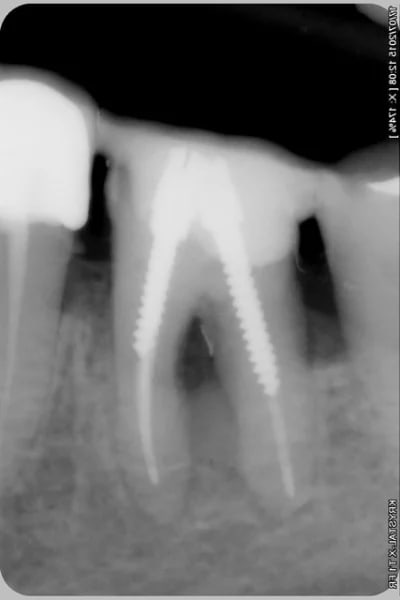

Patiente venant pour son bridge 44-(43)-42-41 mobile avec abces.

Vous lui proposeriez quoi? et comment lui présenteriez vous les choses?

Elle n'a absolument pas conscience de son probleme sur 33

Je pensais lui poser 3 implants en 43-41-33 et tout extraire le bloc incisivo canin mandibulaire...avec des extractions stratégiques de 31 et 32. (en plus du traitement parodontal pour la poche en distal de 35)

Pour moi c'est sans espoir... et extractions 42/41 et 33

En fait c’est le même problème qui se répète d’abord la 43 et ensuite la 33.

J'ai vraiment un doute pour la 33 que je tenterais car il n'y a jamais rien eu de fait, il y aurait un traitement endodontique j'aurais dit avulsion; 41 et 42 si c'est très mobile c'est vrai que ça sent mauvais.

Si vraiment c'est foutu pour toi (dans ce cas là ton plan de traitement est évidemment cohérent), tu lui montres les radios, le niveau osseux, la taille de la lésion. Ca devrait suffire pour qu'elle comprenne les extractions 41, 42, 33.

Pour 31 et 32 tu lui dit simplement que vu le niveau osseux elles seront perdues dans quelques années et que tu auras un résultat plus prévisible, plus esthétique, plus économique et plus durable si on choisit l'avulsion maintenant pour un bridge implanto-porté.

Alors que si on attends, cela veut dire à la perte de 31-32 poser de nouveaux implants, ou exploiter des implants qui n'auront pas été posés de manière optimale en refaisant un bridge: nouveaux travaux, coût plus important, période d'édentement ou d'amovible.